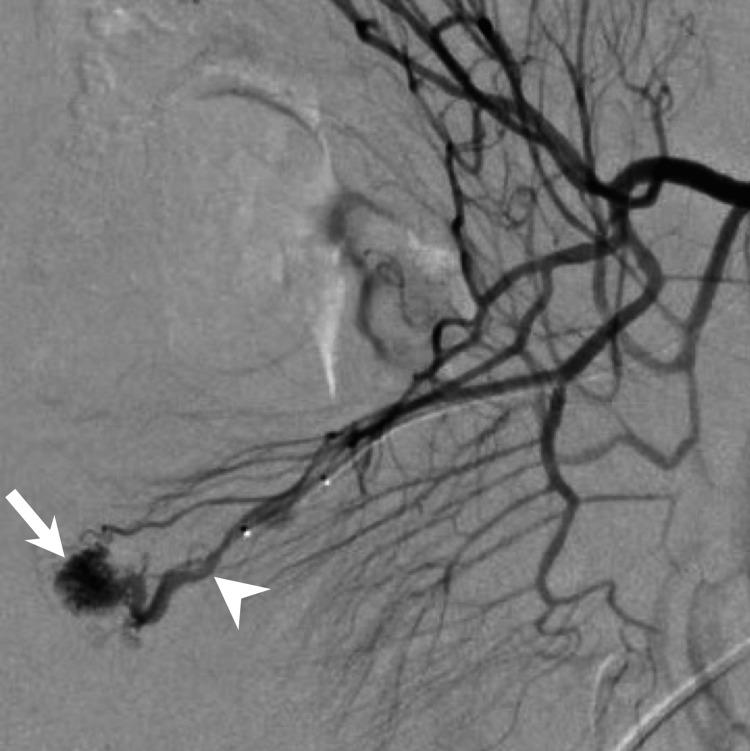

Small bowel arteriovenous malformation (AVM) is a rare vascular lesion, which should be considered in patients presenting with gastrointestinal bleeding, as it is a high-flow arterial lesion that can cause life-threatening bleeding. Although a primary endoscopic examination is performed in cases of suspected small bowel bleeding, the diagnosis of the causal lesion is sometimes difficult. We are presenting a case of small bowel AVM that could not be diagnosed endoscopically but was successfully detected using multiphase CT images with an appropriate protocol. The AVM diagnosis was confirmed using digital subtraction angiography. An endovascular coil is placed in the draining vein as a surgical resection marker. The AVM was resected successfully without any complications.

小肠动静脉畸形(AVM)是一种罕见的血管病变,对于出现胃肠道出血的患者应考虑到这种病变,因为它是一种高流量动脉病变,可导致危及生命的出血。尽管在疑似小肠出血的病例中会进行初步内镜检查,但有时很难诊断出病因性病变。我们现报告一例小肠AVM,内镜检查未能诊断出来,但通过采用适当方案的多期CT图像成功检测到了该病变。通过数字减影血管造影术确诊为AVM。在引流静脉中放置了一个血管内线圈作为手术切除标记物。成功切除了AVM,未出现任何并发症。